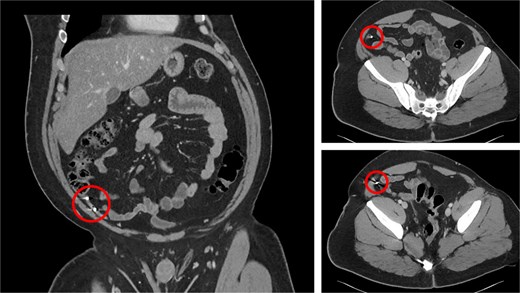

A 30-year-old gentleman with a medical history relevant for asthma and no previous abdominal surgeries presented to the emergency department (ED) at Saint Mary’s Hospital, Rochester, MN, USA, for acute abdominal pain. He described a longstanding history of intermittent right lower quadrant pain, amounting to more than a year and a half. His pain worsened the day prior to his presentation to the ED while attempting to have a bowel movement. On the physical exam, he endorsed a focal tenderness to the right lower quadrant with deep palpation. His laboratory values did not show any derangements, with a hemoglobin level of 15.4 g/dl and a total white blood cell count of 8.6 × 109/l. A computed tomography (CT) scan of the abdomen and pelvis was performed and demonstrated the presence of two rounded, identical metallic bodies in the appendix, measuring up to 5 mm, with no signs of acute appendicitis (Fig. 1). Upon further investigation, it was discovered that the patient was an avid hunter who regularly consumed his game. He was subsequently consented for a laparoscopic appendectomy and taken to the operating room. The abdomen was entered in the standard fashion, and three laparoscopic ports were placed. The appendix was quickly identified in its normal anatomical position, and mild inflammation was noted (Fig. 2). A 45 mm tan Endo GIA stapler was utilized to staple across the base of the appendix, which was then removed via an Endo Catch bag through a 10 mm port. It was opened on the back table, and two small pellets were identified to be consistent with preoperative imaging (Fig. 3). The specimen was sent to the pathology laboratory, which confirmed the diagnosis of acute appendicitis. The patient tolerated the procedure well and was eventually discharged home on postoperative day one.